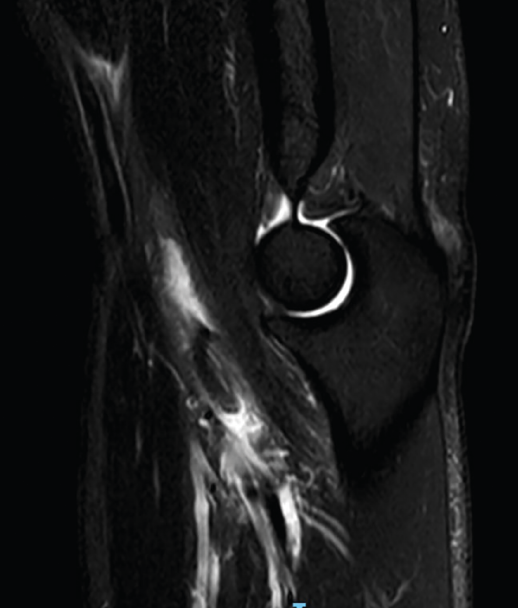

Las lesiones del tendón distal del bíceps varían desde la bursitis bicipitorradial hasta las roturas completas, pasando por las tendinosis y las lesiones parciales. Una buena historia clínica y una exploración física meticulosa aportan gran cantidad de información a la hora de orientar el diagnóstico, que se puede apoyar en la ecografía y la resonancia nuclear magnética para confirmar el diagnóstico y descartar otras entidades plausibles. En el caso de la bursitis bicipitorradial, la tendinosis y las lesiones parciales, el tratamiento inicial debe ser conservador salvo en casos concretos. Las roturas completas agudas deben tratarse de forma quirúrgica excepto en pacientes con baja demanda física o no aptos para tratamiento quirúrgico, sin sobrepasar las 4 semanas de evolución. En caso de diagnóstico tardío y roturas crónicas, las alternativas son la reparación primaria o la reconstrucción con autoinjerto o aloinjerto. Tras la cirugía, es imprescindible seguir un protocolo de rehabilitación que progrese en la ganancia del balance articular y la fuerza sin alterar el proceso de cicatrización. El objetivo de este artículo es presentar las distintas lesiones del bíceps distal, los métodos diagnósticos más adecuados y las alternativas terapéuticas para cada una de las entidades patológicas, para lo que se ha llevado a cabo una revisión bibliográfica a través del motor de búsqueda PubMed de artículos en inglés con referencia al tema seleccionado.

Distal biceps tendon injuries vary from bicipitoradial bursitis to complete rupture, including tendinosis and partial rupture. A good patient history and physical examination provide a great amount of information when trying to establish diagnosis helped by ultrasound and MRI to confirm our suspicion and make a differential diagnosis. Initial treatment for bicipitoradial bursitis, tendinosis and partial rupture should be conservative except in some concrete patients. Complete acute ruptures should be managed by surgical treatment except in low demand patients or patients with concerns regarding anesthesia or surgery. This surgery should be performed before 4 weeks after initial trauma. In case of delayed diagnosis or chronic ruptures, the different alternatives are primary reparation or reconstruction with autograft or allograft. After surgery a rehabilitation program is essential to improve range of motion and strength without stressing the healing process. The main purpose of this manuscript is to present different distal biceps injuries, the most adequate ways to establish a diagnosis and treatment alternatives for every kind of lesion. That is why a revision has been performed through PubMed search engine regarding the selected issue.